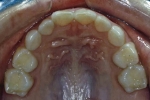

| 初診時